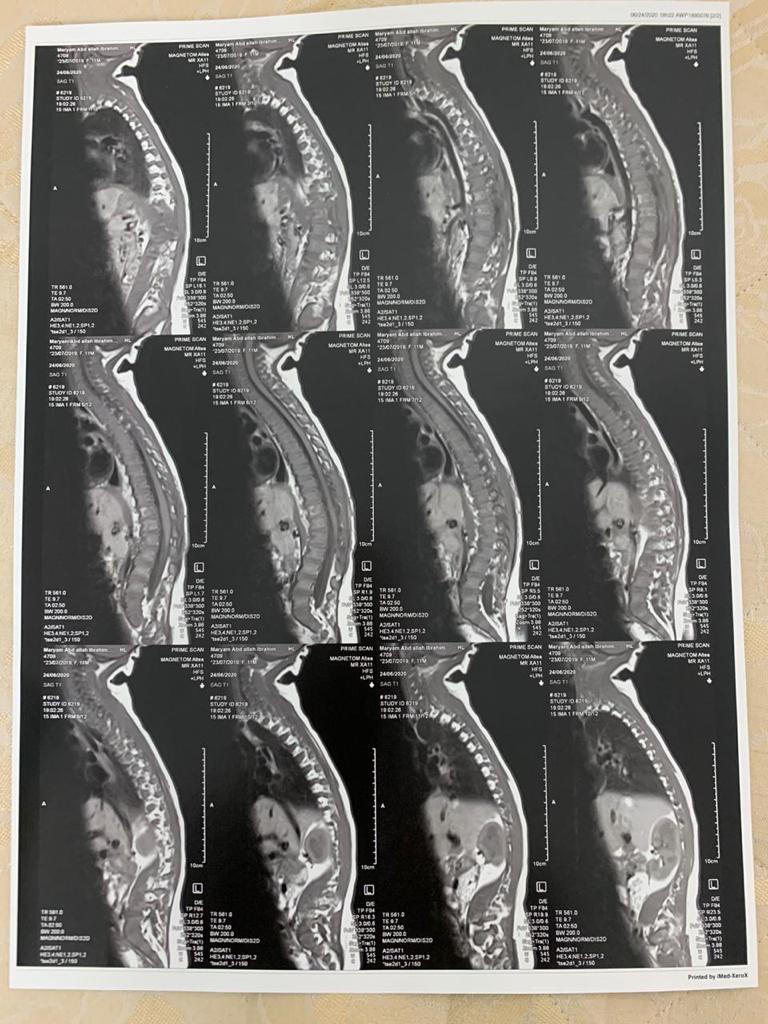

وقال إبراهيم، إن ابنته تبلغ من العمر سنتين و3 أشهر، ومصابة بورم في العضلات الرخوة، بالإضافة إلى ضغط الورم على النخاع الشوكي.

وتابع الأب: لم يتم تشخيصها بالشكل الدقيق، ولكن بعد مرور 55 يومًا من رحلة العلاج، تبين إصابتها بورم في العضلات الرخوة، وذلك بعد إجراء العديد من الفحوصات الطبية، مع ورسم للعصب، والاشاعات.

وواصل الأب: بعد ما عرفنا مرضها عملت عملية استئصال الورم، ولاقينا الورم ضاغط على النخاع الشوكي، لكن فضل 5 ملي منه موجود، وبعدين مشينا في رحلة الكيماوي.

واستكمل الأب: خضعت مريم لـ 13 جلسة كيماوي لمدة عام، لتحديد حجمه، ولكن بعد مرور 8 أشهر زاد حجم الورم مجددًا بقدر 8 سم، مضيفًا: كان لازم تاخد كيماوي تاني وتعمل رسم عصب، وبعدين أشعة وعملية تانية.